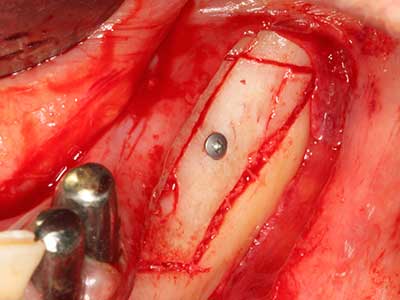

Indication: Bone grafting

Autologous bone transplants are used in the form of blocks, shells, rings and are also combined with bone replacement materials as chips. If the implant site is prepared at the same time as the augmentation, various bone filter systems have proven effective for collecting the resulting bone chips. As an alternative, the implant site can be prepared using a low-speed device without irrigation. If an implant is not inserted, bone chips can be harvested from the periphery with bone scrapers. This is also possible with piezo surgery using specialized attachments that yield higher-quality bone chips compared chips harvested with round drills, as has been confirmed in a study comparing the two methods (Chiriac, Herten et al. 2005).

Piezo surgery has additional advantages when harvesting bone blocks. In addition to the high precision with osteotomy described above, the use of the thin saw tips specifically minimizes loss of material. Greater loss of material during harvesting can be expected with the thicker instrument tips, particularly when using Lindemann drills (Lakshmiganthan, Gokulanathan et al. 2012). The basal separation, which is necessary particularly for retromolar block transplants, is simplified by specially designed rectangular saws, with the result that piezo surgery is viewed as a precise, simple and safe procedure for harvesting retromolar bone blocks (Happe 2007) (Fig. 1-12).